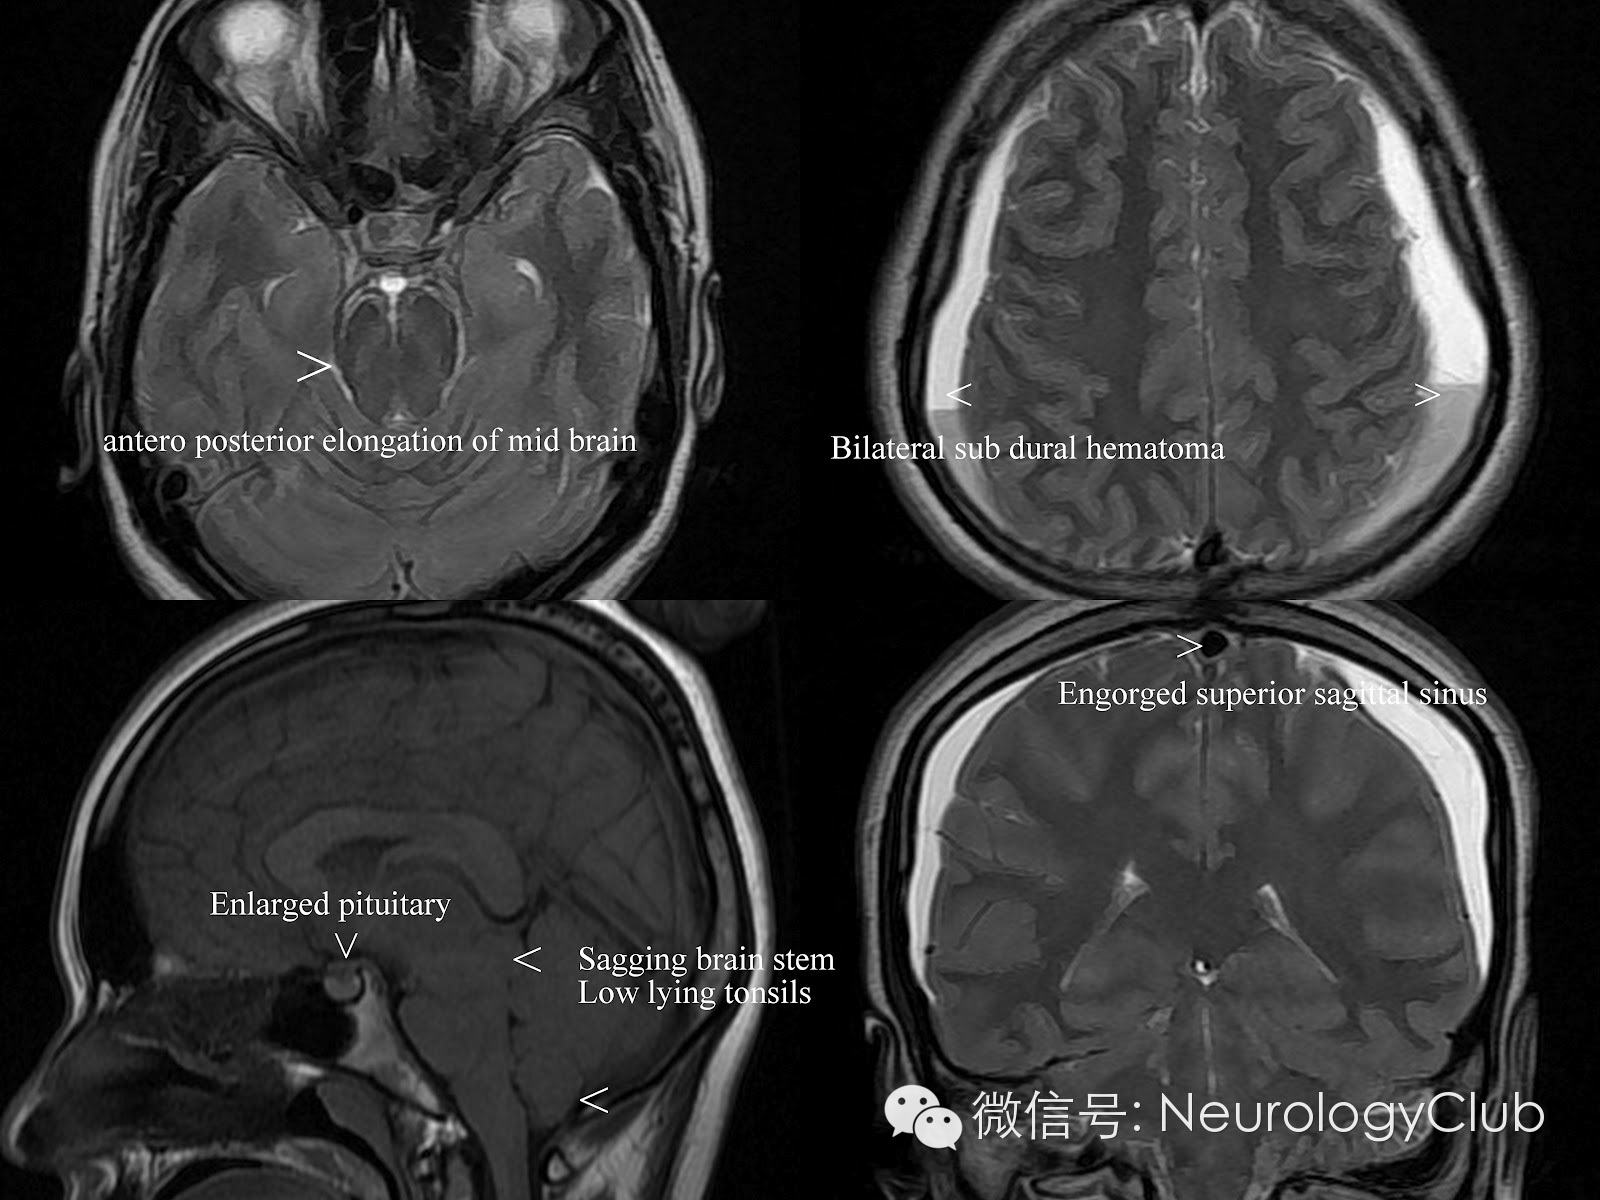

根据Monro-Kellie假说,颅内腔容积恒定不能扩张,颅内容物的总量之和即脑组织、脑血流量及脑脊液量的总和应保持恒定不变。如果其中一种成份增加必然导致另外两种成份的减少;反之,当颅内低压综合征患者的脑脊液容量减少时,必然导致另外两种成份增加。由于脑组织容积相对恒定,所以只能依靠脑血流量的变化起到代偿作用。因为软脑膜及脑实质血管有血脑屏障而硬脑膜没有,所以这种静脉的充血扩张只能表现在硬脑膜和脑静脉窦上。影像学则相应地表现为硬脑膜、硬脊膜弥漫性增厚、增强以及颅内静脉窦的扩张,垂体硬膜充血则表现为垂体增大。如果脑静脉充血扩张仍不能完全代偿,还可进一步表现为硬膜下积液。另外,在正常情况下,脑组织是漂浮在脑脊液中的,在脑脊液容量减少时,脑脊液对脑组织的浮力作用下降使脑组织向下移位,称为下垂脑,构成了影像学上的另外一组表现。

硬膜下积液表现为双侧对称性薄层积液,无占位效应,对下面的脑沟脑裂无压迫效应。

增强扫描时硬脑膜弥漫性增强增厚是颅内低压综合征的最具特征性表现,也是阳性率最高、出现最早的MRI表现。呈不间断的线样增强,无局限性结节,同时经常伴有硬脑膜增厚和皮层静脉的扩张,但从不累及软脑膜。

(3)静脉结构充盈(Engorgement of venous structures)

(静脉窦扩张变圆)

(4)垂体充血(Pituitary hyperemia)

(5)脑组织下沉(Sagging of the brain)